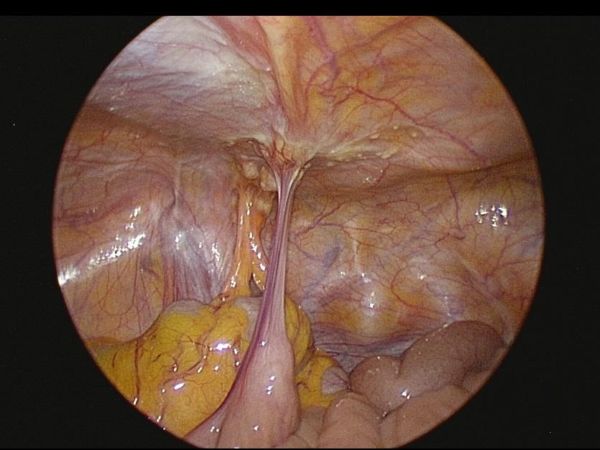

在腫瘤反應與身體條件允許下,醫療團隊進一步評估後,建議接受「腹腔高壓氣霧化學治療(PIPAC)」。此為以腹腔鏡進行的微創治療方式,將化療藥物於高壓環境中霧化,使藥物能較均勻分佈於腹腔內,作為部分腹膜癌病人之治療選項之一。陳先生完成一個療程、共三次「腹腔高壓氣霧化學治療(PIPAC)」 後,臨床症狀與檢查結果顯示病情獲得控制,相關評估指標亦呈現改善趨勢。